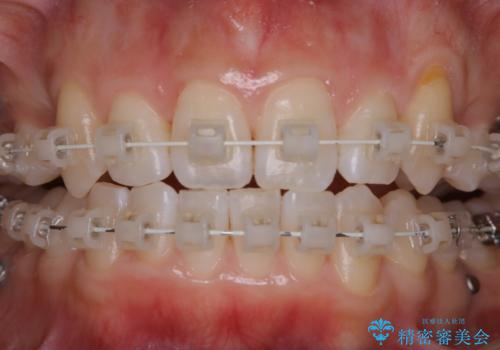

ワイヤー矯正中のPMTC

- ワイヤー矯正中に装置の周りの着色が気になるとのことで来院されました。PMTC30分コースを行いました。

ワイヤー矯正中も、歯の表面に着色(ステイン)が付着することがあります。着色(ステイン)が付着したままだと審美的な問題以外にも、虫歯を発見しずらいことや、細菌が繫殖しやすくなることがあります。クリーニングを行うことで、虫歯や歯周病予防に効果的だったり、もちろん見た目も審美的です。クリーニング後には、汚れが取り除かれ、お口の中がスッキリ・爽快感で気持ちがよくなります。矯正中も定期的にPMTCを行うことが大切です。